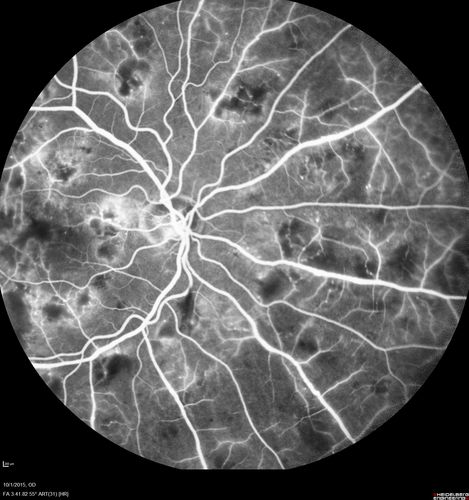

Hairy Cell Leukemia - Retinal Hemorrhage and twig Branch Vein Occlusion

79 year old man He has had hairy cell leukemia since 2002.  He is in remission.  His last blood tests were 9/2018.  He just moved down here and needs a new leukemia doctor.  His vision is fine.

VA OD: Dcc20/25

VA OS: Dcc20/25

IOP: TP: OD:12 OS:12